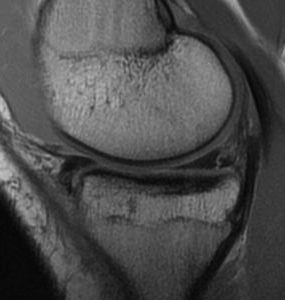

1. Longitudinal Tears

Most common

- vertically oriented tear parallel to edge of meniscus

- usually of posterior part of meniscus

- may occur in either meniscus

- extent varies

B. Complete

C. Bucket handle

- displaces into intercondylar notch

- may be central or peripheral

- cause of locked knee

- can damage chondral surface over time